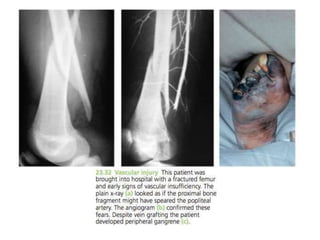

VASCULAR

INJURY

Injur

y

Vess

el

First rib

fracture

Subcalvia

n

Shoulder dislocation

Axillar

Humeral supracondylar fracture Brachial

Elbow dislocation

Brachi

al

Pelvic fracture Presacral and internal iliac

Femoral supracondylar fracture

Femor

Knee dislocation Popliteal

Proximal tibial Popliteal or its

branches

Clinical features

• Paraesthesia or numbness

• Injured limb is cold and pale or

slightly cyanosed

• Weak or absent pulse

Treame

nt

• All bandages and splints should be

remove

• Fractures re-x-rayed and if artery is

being compressed prompt reduction is

required

• Circulation reassessed repeatedly over

the next half hour

• If no improvement, vessels must be

explored by operation with pre or

peroperative angiography

• Cut vessel can be sutured, or a segment

may be replaced by a vein graft, if it is

thrombosed, endarterectomy may restore

blood flow

• If vessel repair is done, stable fixation is

a must and fracture should be fixed

internally